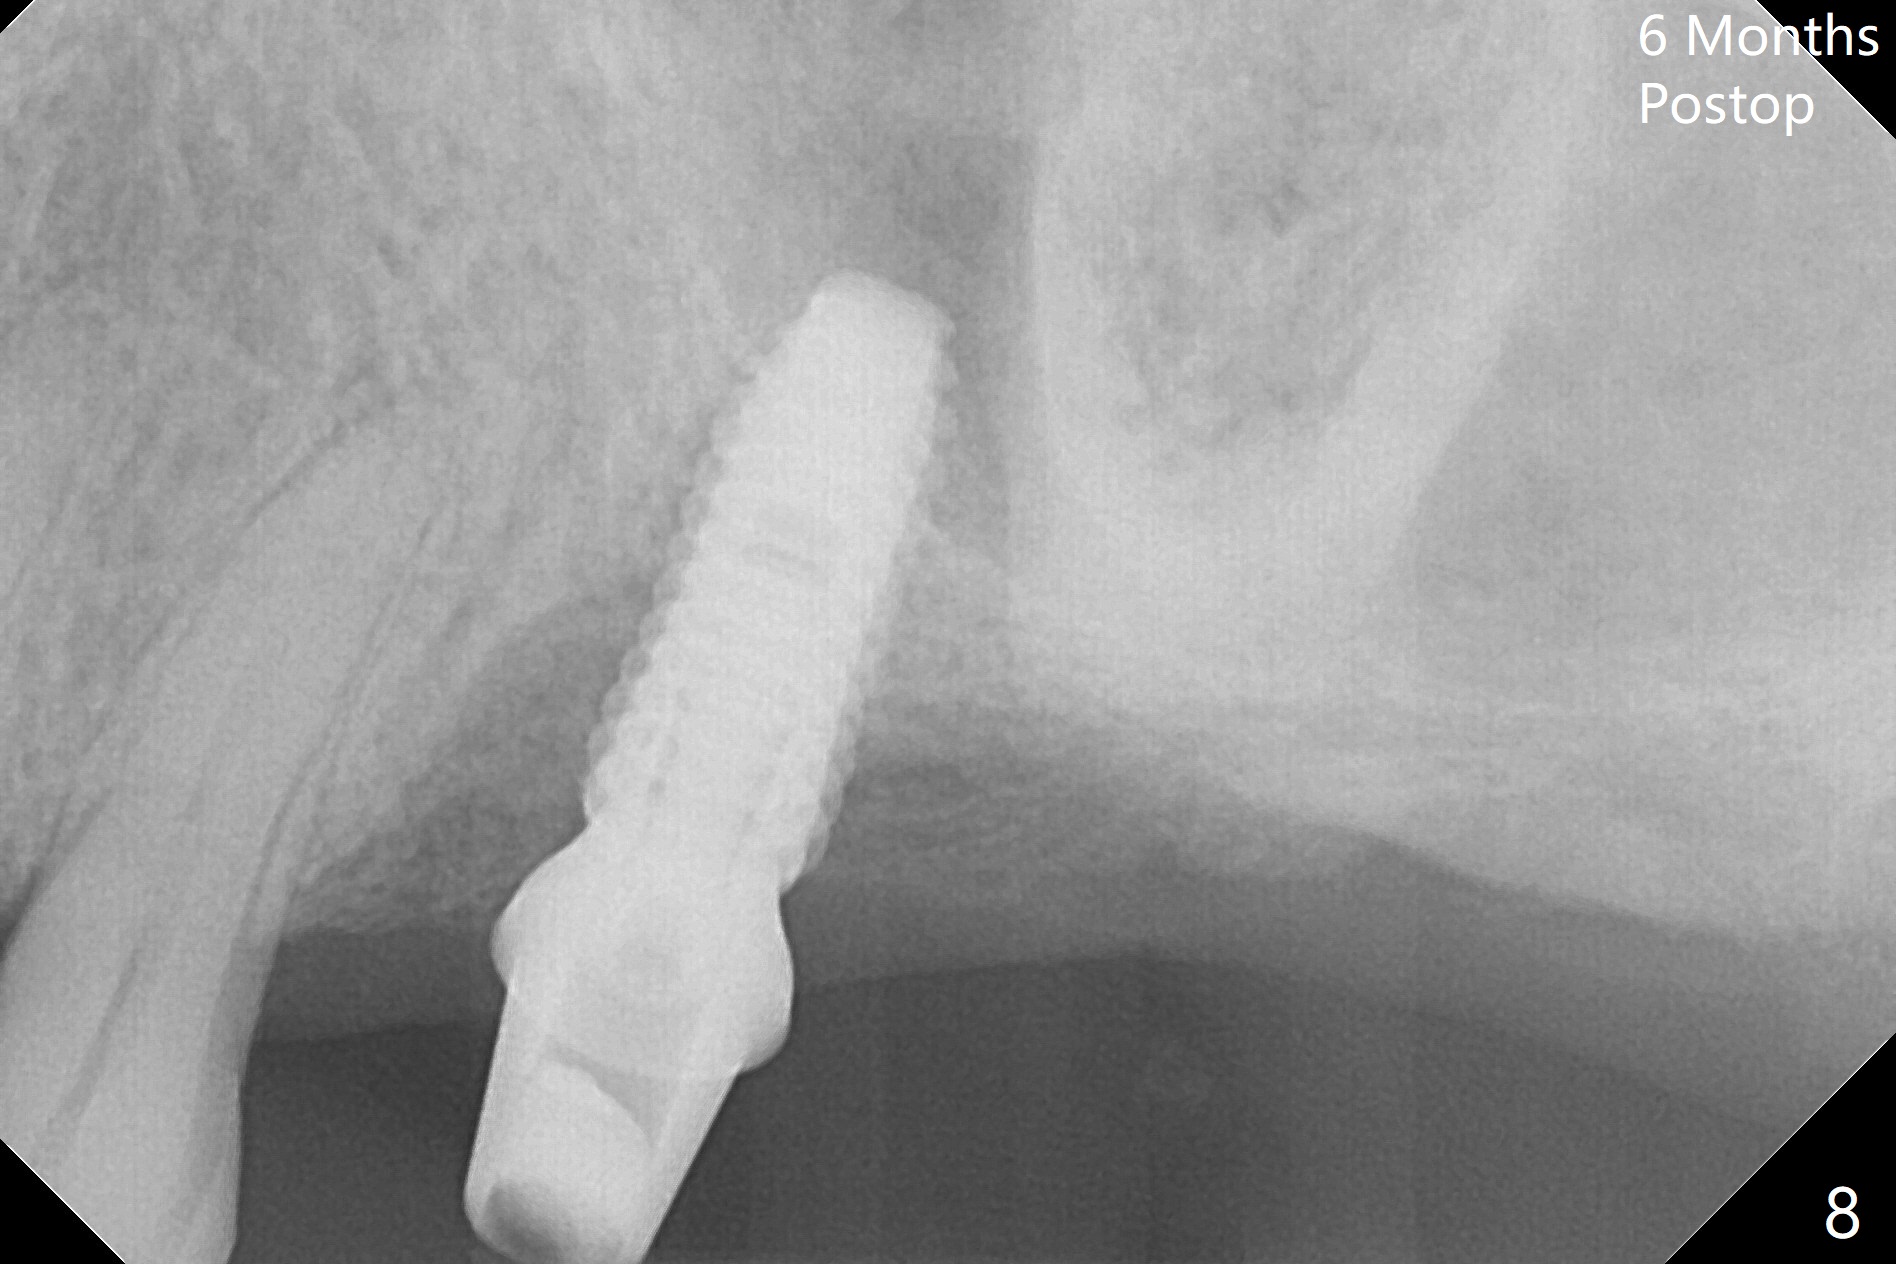

Buccal gingival recession at #14 (Fig.1) is less severe than the palatal one (Fig.2).  Without raising the buccal gingiva (Fig.3 B), osteotomy in the septum is established apparently in the middle socket (Fig.3 *, 4).  As the osteotomy increases with 3.8 mm drill, the palatal wall of the osteotomy starts to be perforating.  When a 4.5x11.5 mm implant is placed, palatal threads are exposed, to which autogenous bone and Vera Graft are placed (Fig.5 *).  After placement of a 5.5x5(3) mm abutment, an immediate provisional (Fig.6 P) is fabricated to cover the sockets.  If the septal dimension were studied carefully by raising the buccal gingiva slightly, the osteotomy could be initially more buccal so that the palatal thread exposure could be less.  When the provisional is removed 1.5 months postop, the implant is exposed palatally.  The margin of the provisional is modified so that the implant can be cleaned by the patient using Water Pik.  In fact, the healthy gingiva seems to be attached to the implant threads 2 weeks later (Fig.7).  The distal implant threads remains exposed 6 months postop; it appears that the distal socket wall has resorbed (Fig.8).  The sockets heal 1 year 7 months post cementation (Fig.9).